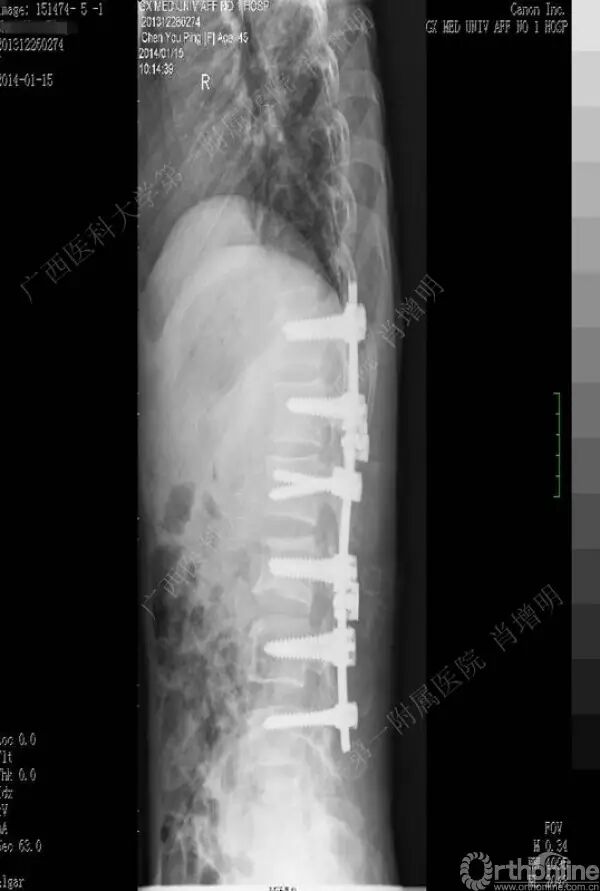

退变性脊柱侧凸是由于椎间盘退变后继发小关节退变,椎管和神经根管容积变化以及脊柱失稳,畸形等病理改变,以疼痛和神经压迫症状为主要表现的常见疾病。

退变性脊柱侧凸多发于50岁以上的中老年群体,是现代常见的老年疾病。多年来,针对该病的临床研究一直没有停步,广西医科大学第一附属医院肖增明教授细致地介绍了该病的诊疗进展。